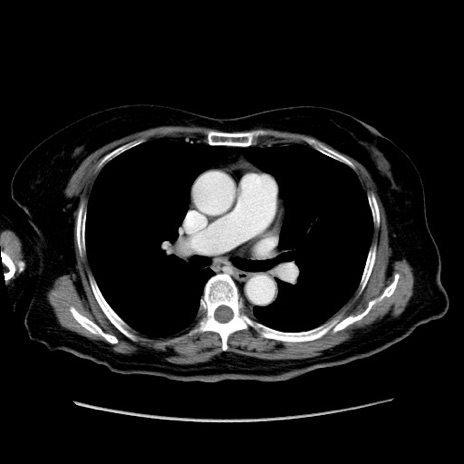

症例19(横断像)

【症例】80歳代女性

【主訴】下腹部痛

【現病歴】約8時間前より下腹部痛の出現あり、救急外来受診。

【既往歴】両側付属器切除

【身体所見】意識清明、下腹部正中に手術痕あり、その部位に一致して圧痛と反跳痛あり。腸蠕動音は亢進。

【データ】WBC 9300、CRP 0.15